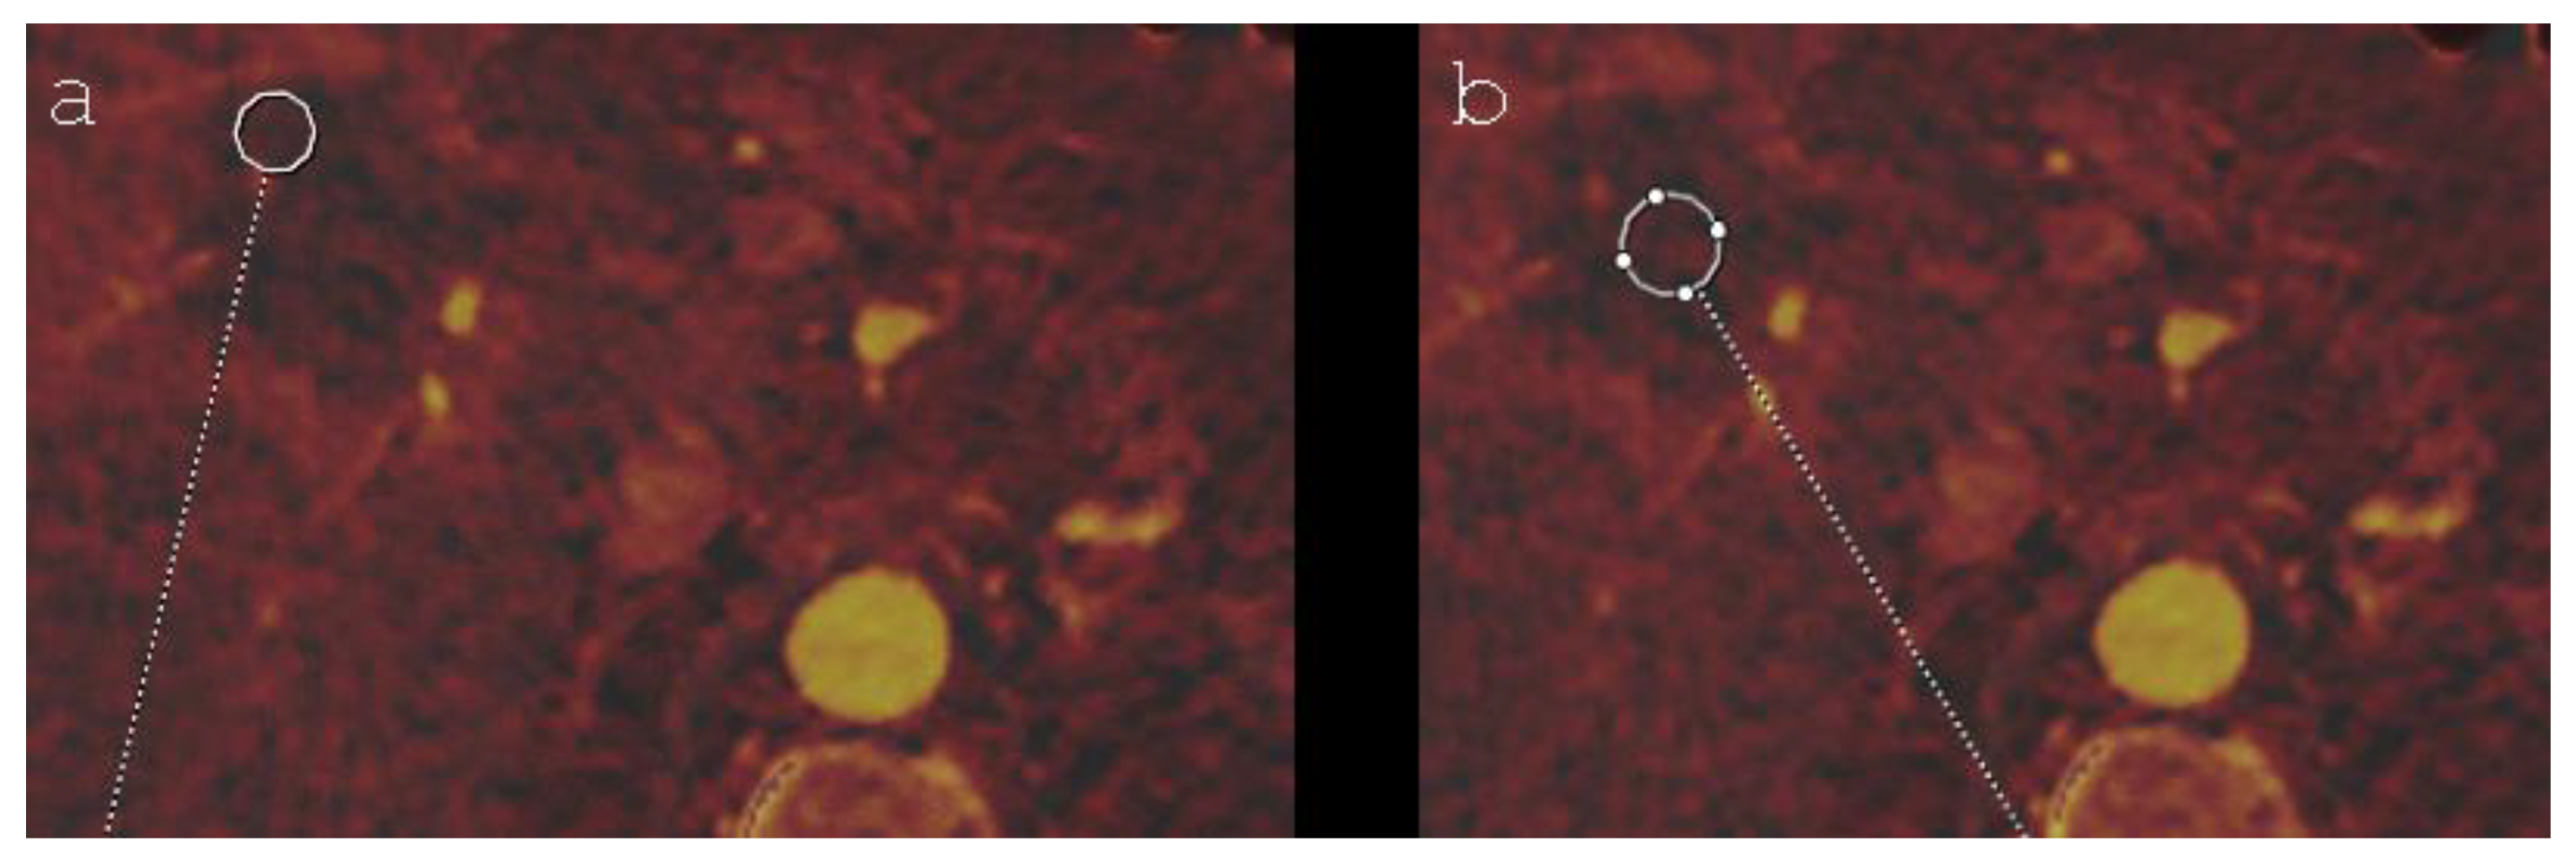

- Bäumler, W.; Wiggermann, P.; Lürken, L.; Dollinger, M.; Stroszczynski, C.; Beyer, L.; Schicho, A. Early detection of local tumor progression after irreversible electroporation (IRE) of a hepatocellular carcinoma using Gd-EOB-DTPA-based MR imaging at 3T. Cancers 2021, 13, 1595. [Google Scholar] [CrossRef] [PubMed]